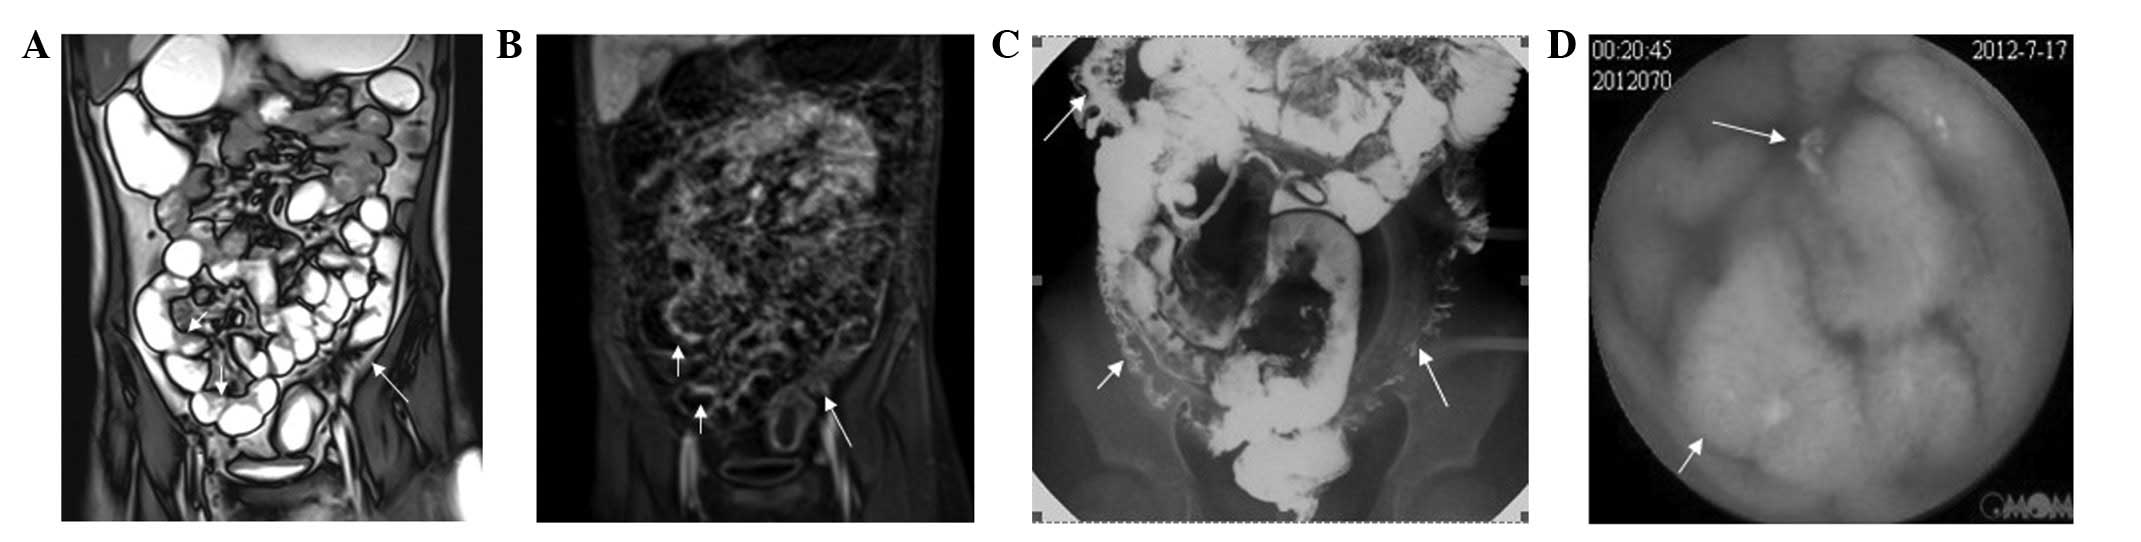

MRI clearly shows all cases with bowel disease. Among the 55 cases, 37 cases involved the small intestine (distal ileum) while 49 cases involved the colon, including the sigmoid colon, rectum, descending colon and ascending colon. An inflamed bowel was observed in a number of cases, with an average of 2.7 lesions per case. In these cases, enhanced MRI demonstrated a significantly augmented intestinal wall with an increased thickness of 5–14 mm. The majority of the lesions thickened circularly and unevenly, which narrowed the lumen (Fig. 1). Cellulitis or inflammatory masses were formed around the bowel presenting related mesenteric fat hyperplasia, fibrosis, thickening, short T1 high signal and significantly widened intestinal clearance (Figs. 2 and 3). Mesenteric lymph node enlargement and retroperitoneal lymph node enlargement were observed in three patients, while six cases presented ascites. Fistulae were not observed between the small intestine and colon; however, four cases with abdominal wall fistula and two cases with anal fistula were observed.